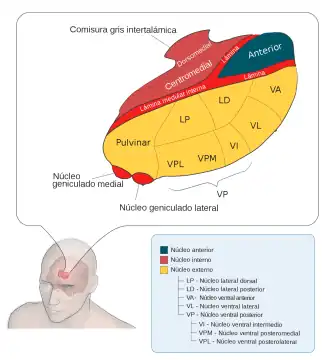

El tálamo es una estructura par con forma ovalada. Mide alrededor de 3 cm de largo y representa el 80% del diencéfalo, el 20% restante lo forma el hipotálamo y el epitálamo. Está constituido por núcleos de sustancia gris dispuestos entre tractos de sustancia blanca. Lo atraviesa en toda su longitud una estructura vertical que recibe el nombre de lámina medular interna que lo divide en dos partes y está formada por sustancia blanca que conecta los núcleos talámicos entre sí. El tálamo del lado derecho se une con el izquierdo mediante la comisura gris intertalámica que actúa como un puente entre ambas formaciones.[1]

Los núcleos del tálamo pueden dividirse en cuatro regiones principales, cada una de los cuales está formada por uno o varios núcleos de neuronas:[1]

- Grupo anterior. Incluye el núcleo anterior.

- Grupo medial. Incluye los núcleos mediales.

- Grupo lateral. Incluye el núcleo lateral dorsal, núcleo lateral posterior y núcleo pulvinar.

- Grupo ventral. Está formado por cinco núcleos.

- Otros. Núcleos intralaminares, núcleo de la línea media y núcleo reticular.